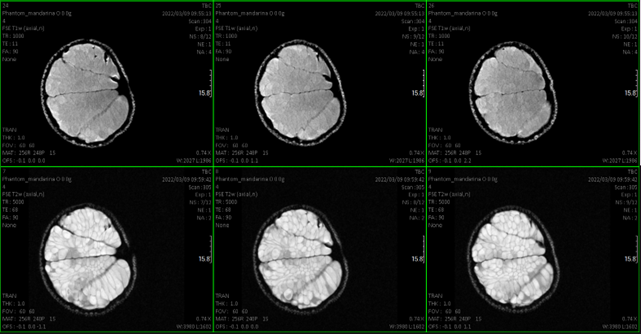

The service includes the housing of mice or rats to be able to carry out longitudinal studies, the administration, if applicable, of contrast agents, or radiopharmaceuticals for PET. Acquisition of both T1-weighted and T2-weighted images, as well as colocalized with the PET image. Volume measurement.

- Qualitative and quantitative studies (relaxation times T1 and T2 and even making maps) at the brain level and other organs.Cardiological sequences: diffusion, determination of blood volume…

- Anatomical and functional studies of different organs (for example: renal, abdominal, liver…).

- Oncological studies to detect and locate tumors and volume calculation.